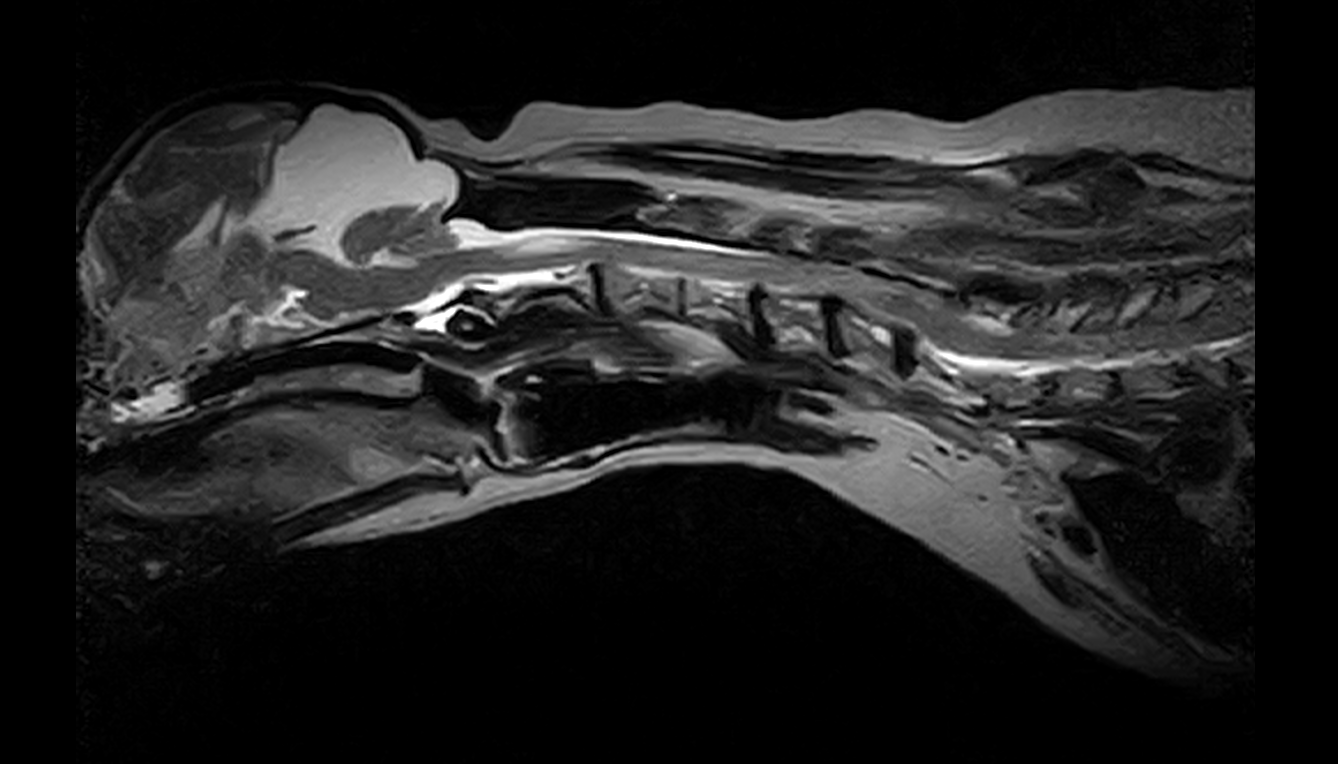

左前肢破行、後肢ふらつきを主訴に来院しました。CT・MRI撮影より、C5-6の椎間板ヘルニア、小脳背側のくも膜下嚢胞が認められました。症状が軽度から中等度、また小脳背側にくも膜下嚢胞が認められ麻酔のリスクなどを考慮し、まずは内科療法から行いました。2か月後症状の改善が認められず、症状も進行し、起立・歩行困難となりました。

左前肢破行、後肢ふらつきを主訴に来院しました。CT・MRI撮影より、C5-6の椎間板ヘルニア、小脳背側のくも膜下嚢胞が認められました。症状が軽度から中等度、また小脳背側にくも膜下嚢胞が認められ麻酔のリスクなどを考慮し、まずは内科療法から行いました。2か月後症状の改善が認められず、症状も進行し、起立・歩行困難となりました。

C5-6椎間板ヘルニア、小脳背側くも膜下嚢胞

C5-6椎間板ヘルニア、くも膜下嚢胞と診断した